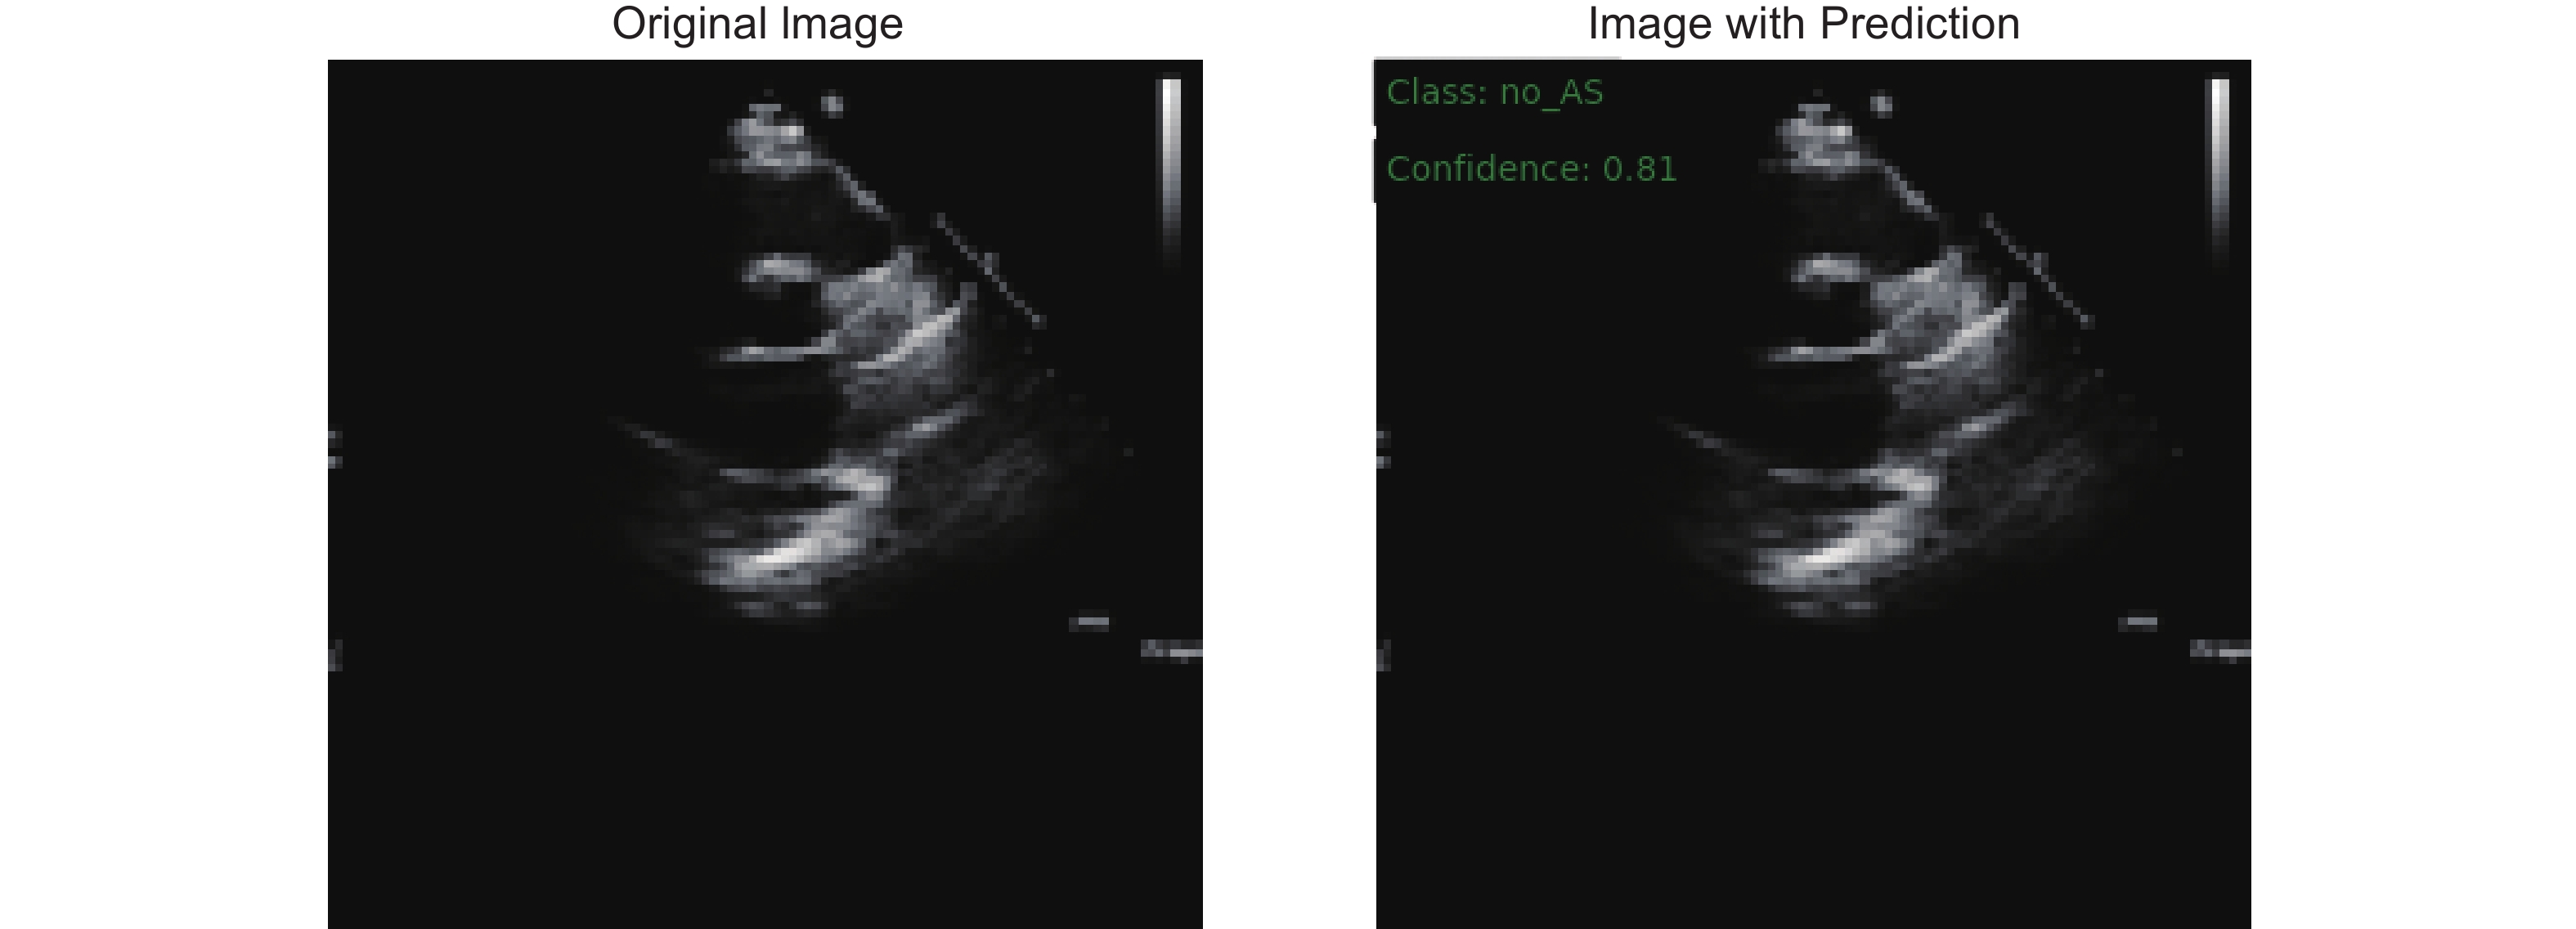

Holste G, Oikonomou EK, Mortazavi BJ, Coppi A, Faridi KF, Miller EJ, et al. Severe aortic stenosis detection by deep learning applied to echocardiography. Eur Heart J 2023; 44: 4592-4604.

Krishna H, Desai K, Slostad B, Bhayani S, Arnold JH, Ouwerkerk W, et al. Fully automated artificial intelligence assessment of aortic stenosis by echocardiography. J Am Soc Echocardiogr 2023; 36: 769-777.

Huang Z, Long G, Wessler BS, Hughes MC. Tmed 2: a dataset for semi-supervised classification of echocardiograms. In DataPerf: Benchmarking Data for Data-Centric AI Workshop 2022.

Huang Z, Long G, Wessler B, Hughes MC. A new semi-supervised learning benchmark for classifying view and diagnosing aortic stenosis from echocardiograms. Machine Learning for Healthcare Conference 2021; 149: 614-647.